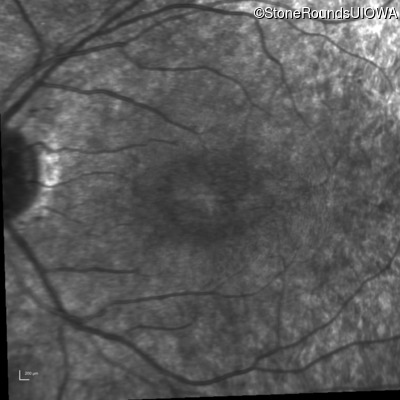

Infrared Fundus Photograph - Right - 20/25 -2

Exemplar

Infrared Fundus Photograph - Left - 20/32